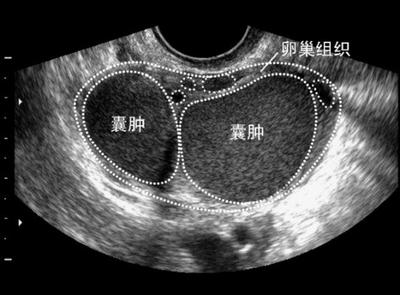

检查显示小娟双侧卵巢巧克力囊肿,右侧有两枚3cm大小的巧克力囊肿,左侧一枚约4cm巧克力囊肿。妇科医生说小娟的痛经与巧克力囊肿有很大关系,建议小娟手术切除双侧巧克力囊肿。鉴于小娟还未婚未育,在小娟月经干净后在腹腔镜下剥离了双侧卵巢上的巧克力囊肿,手术很成功。

卵巢巧克力囊肿是“肿块”但并非是“肿瘤”,它是子宫内膜异位症的一种病变。正常情况下,子宫内膜生长在子宫腔内,受体内女性激素的影响,每月脱落一次,形成月经。如果月经期脱落的子宫内膜碎片,随经血逆流经输卵管进入盆腔,种植在卵巢表面或盆腔其他部位,形成异位囊肿,这种异位的子宫内膜也受性激素的影响,随同月经周期反复脱落出血,如病变发生在卵巢上,每次月经期局部都有出血,使卵巢增大,形成内含陈旧性积血的囊肿,这种陈旧性血呈褐色,粘稠如糊状,似巧克力,故又称“巧克力囊肿”。这种囊肿可以逐渐增大,有时会在经期或经后发生破裂,但很少发生恶变。